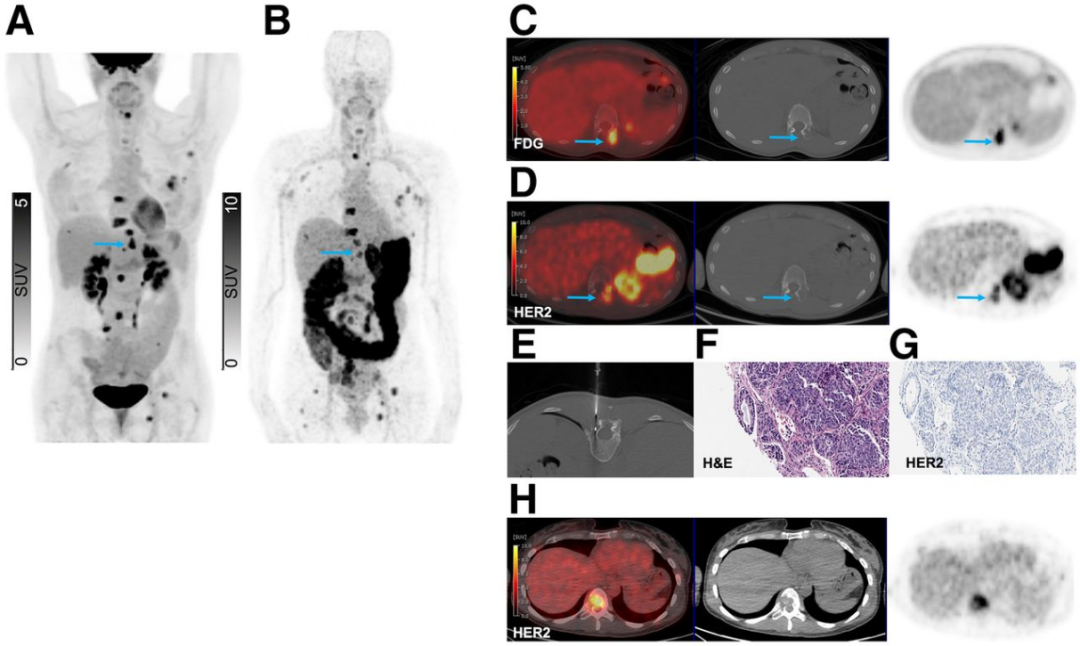

来自89Zr-ss-帕妥珠单抗队列的代表性患者展示了HER2表达的全谱系分布,图2-4展示了不同病例的HER2 PET图像和相应的病理结果。图2显示了一个HER2阳性胸骨病灶,图3显示了同一患者体内的HER2-0和HER2低表达骨病灶,图4显示了一个HER2-0肝脏病灶。

图3. 一例患者HER2 PET显示的HER2-0和HER2低表达骨病灶